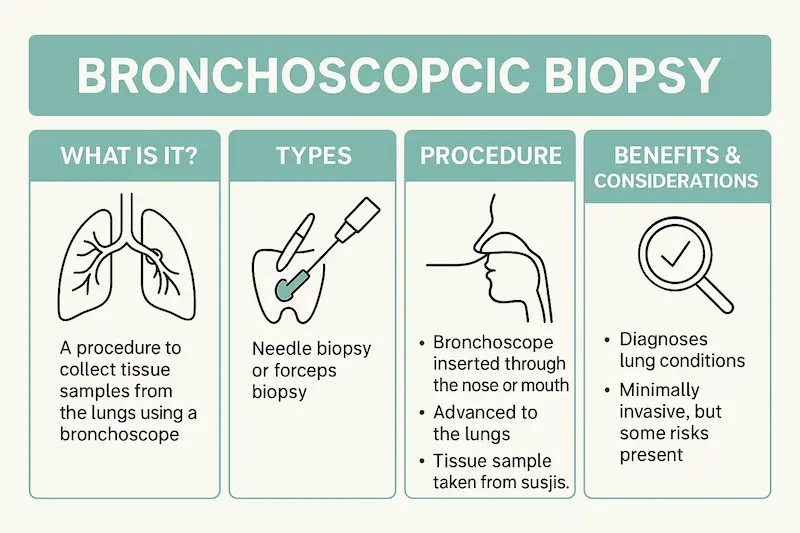

Бронхоскопическая биопсия — это малоинвазивная диагностическая процедура, которая позволяет врачу-пульмонологу или онкологу получить образец ткани (биоптат) из дыхательных путей или непосредственно из легкого для дальнейшего исследования. Ключевая цель — поставить точный диагноз при подозрении на различные заболевания, в первую очередь — рак легких. Процедура выполняется с помощью бронхоскопа, тонкой гибкой трубки с камерой и светом на конце. Проведение бронхоскопической биопсии в Турции гарантирует использование самого современного оборудования, что минимизирует дискомфорт для пациента и повышает точность диагностики.

Виды бронхоскопической биопсии: Эндоскопические и игольчатые методы

Современная пульмонология в Турции предлагает несколько видов биопсии, выбор которых зависит от расположения и размера патологического очага. Ваш врач подберет наиболее подходящий метод для обеспечения максимальной информативности и безопасности. Проведение бронхоскопической биопсии в Турции может включать как стандартные, так и высокотехнологичные подходы, доступные лишь в ведущих мировых центрах.

- Эндобронхиальная биопсия: Врач берет образец ткани непосредственно со стенки бронха, если новообразование видно через камеру бронхоскопа.

- Трансбронхиальная биопсия легкого: Используется для получения образцов ткани из более глубоких отделов легкого (периферии). Специальные щипцы или игла проводятся через канал бронхоскопа к нужному участку под рентгеновским контролем. Это один из самых частых видов биопсии легкого в Турции.

- Эндосонографическая трансбронхиальная аспирационная биопсия (EBUS-TBNA): Это передовой метод, сочетающий бронхоскопию с ультразвуковым исследованием. Он позволяет врачу видеть лимфатические узлы и образования за пределами дыхательных путей и выполнять прицельную пункцию. Этот метод незаменим для стадирования рака легких.

- Навигационная бронхоскопия: Технология, подобная GPS для легких. Предварительно создается 3D-карта бронхиального дерева на основе данных КТ, что позволяет врачу с высочайшей точностью добраться до самых отдаленных и мелких узелков. Этот метод значительно расширяет возможности диагностики легких в Турции.